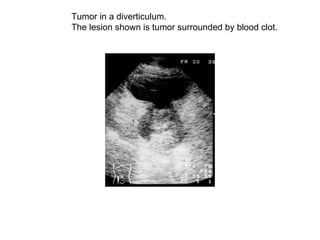

Tumor in a diverticulum.  The lesion shown is tumor surrounded by blood clot.